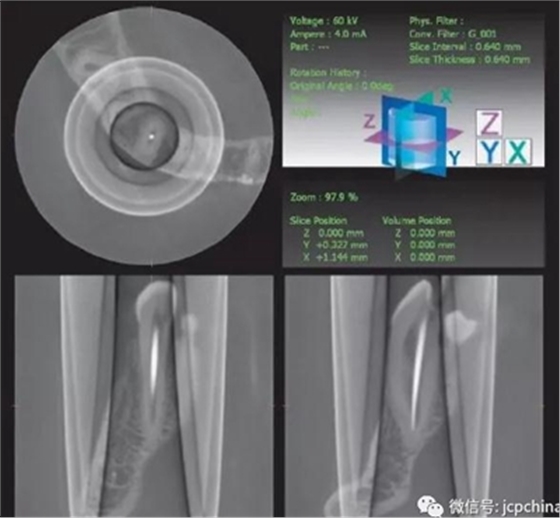

(5)環(huán)形偽影

探測板上的缺陷導(dǎo)致環(huán)形影像。環(huán)形偽影常常圍繞著旋轉(zhuǎn)中心。